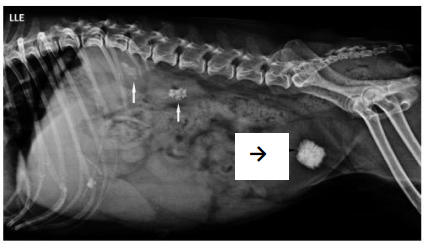

Foi atendida em um Hospital Veterinário Universitário uma cadela

de nove anos da raça poodle com 6,5 kg de peso. O tutor se

queixou de que o animal apresentava apatia, perda de peso e

secreção purulenta e sanguinolenta na vagina. Apresentou

também episódios de vômitos e diminuição da ingestão hídrica.

Foi solicitada uma radiografia látero-lateral esquerda do abdome,

permitindo identificar três pontos indicados na imagem abaixo:

duas setas brancas e uma preta.

As setas brancas e a seta preta mostravam, respectivamente,